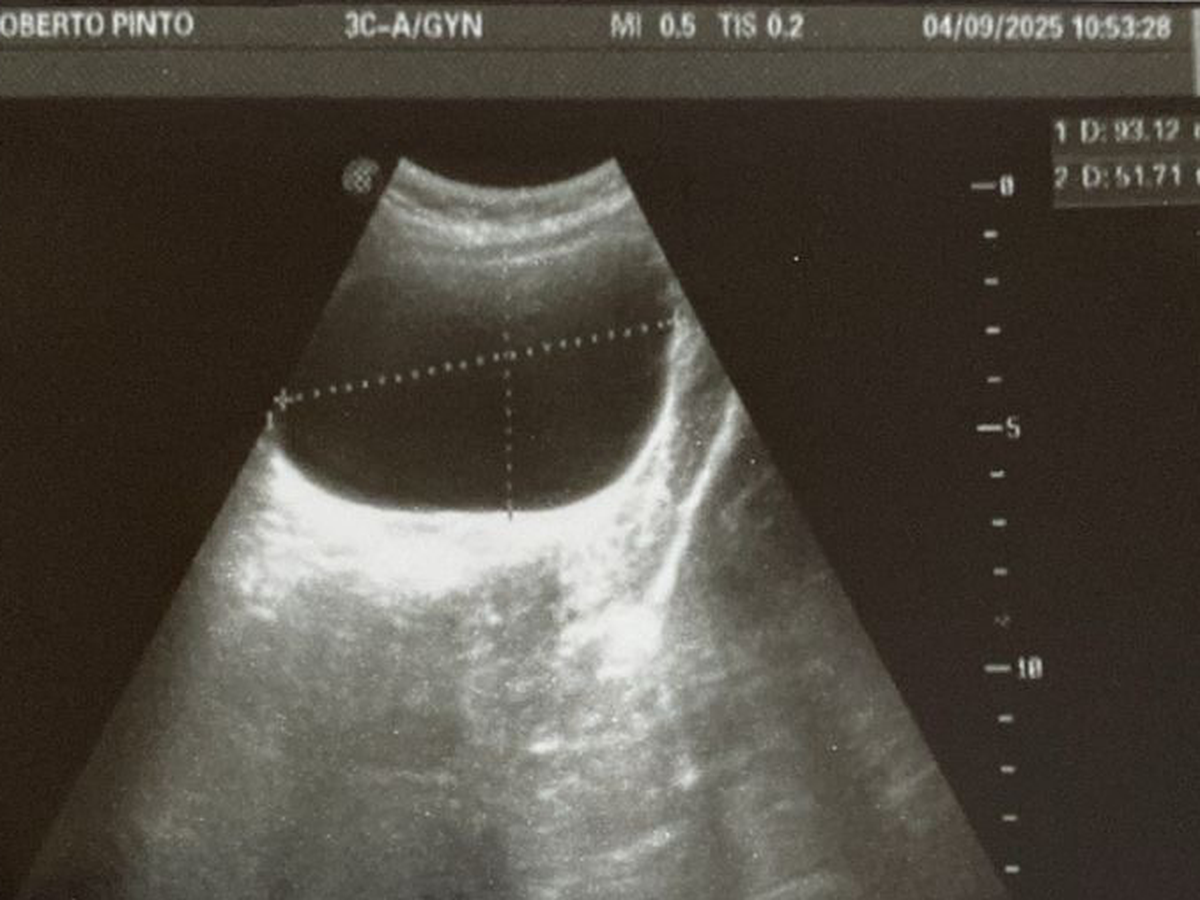

My name is Augusto WahLung, and all my life I've worked as an English as a Second Language teacher. My life changed when I tried to start my own business and failed; this led me to acquire a huge debt, and at this moment, I need help to cover the medical expenses of a surgery for my daughter Andrea. She currently has a cyst on one of her ovaries and must undergo surgery as soon as possible to save her ovary. In a few months, she will need a second surgery to remove a plate that connects one of the bones in her left leg. This plate must be removed so that her bone can grow normally.